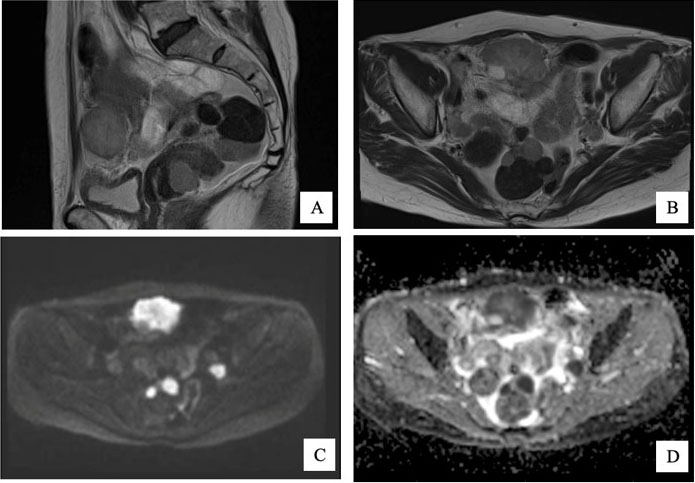

A 59-year-old nicotine-dependent man with reported history of adolescent asthma and chronic obstructive pulmonary disease was referred to pulmonology clinic following a chest X-ray with incidental new findings of upper lobe interstitial nodularity suggestive of granulomatous disease. Upon presentation to pulmonology clinic his only complaints were chronic cough for 10 years duration and exertional dyspnea. Given his radiographic findings high resolution computed tomographic (HRCT) examination and vasculitis workup was ordered. Blood work was only significant for elevated erythrocyte sedimentation rate (ESR) 80 mm/h, elevated C-reactive protein (CRP) 2.3 mg/dL, and elevated eosinophils 5.3% with 0.6×103/uL absolute eosinophils. Tuberculosis Quantiferon test, vasculitis workup, and angiotensin converting enzyme (ACE) levels were within normal limits. High resolution computed tomography examination revealed innumerable tiny bilateral pulmonary nodules consistent with miliary pattern (Figure 1). Bronchoscopy with transbronchial lung biopsy was subsequently performed and found to contain focal areas of histiocytes associated with CD1a positive cells on immunohistochemistry, confirming PLCH (Figure 2). The patient was educated on the disease progression and thus strongly advised with smoking cessation. Exertional dyspnea symptoms were controlled with long-acting bronchodilator and inhaled corticosteroid.

Figure 1: High resolution chest CT with contrast. (A) Parenchymal window. Notice the peripheral tree-in-bud formation and bilateral diffuse nodular (1–2 mm) distribution without coexisting cystic formation that normally exists with PLCH. (B) Coronal slice. Nodular distribution extending throughout the upper, mid, and lower lung fields.